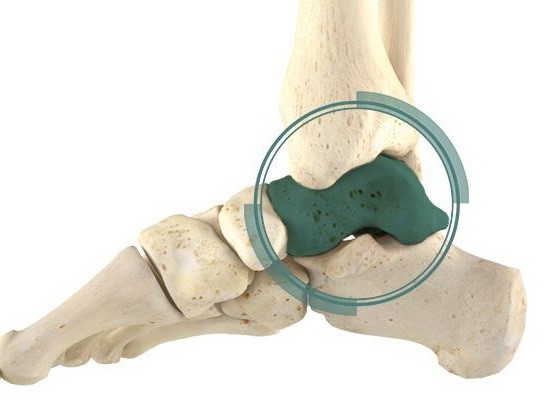

Таранна кістка (talus) займає унікальне анатомічне положення в архітектурі гомілковостопного та підтаранного суглобів, виконуючи критичну роль у біомеханіці стопи та гомілки. Переломи цієї кістки становлять приблизно 0,1-0,85% усіх переломів скелета та близько 3-6% переломів кісток стопи, що робить їх відносно рідкісною, проте клінічно значущою травмою опорно-рухового апарату.

Рентгенографія залишається первинним методом візуалізації. Стандартні проекції включають передньозадню, бічну та mortise-проекцію гомілковостопного суглоба, а також передньозадню, бічну та косу проекції стопи. Додаткова проекція Canale (стопа в положенні підошвового згинання 15°, пронації 15° з направленням променя під кутом 75° до горизонталі) оптимізує візуалізацію шийки таранної кістки.